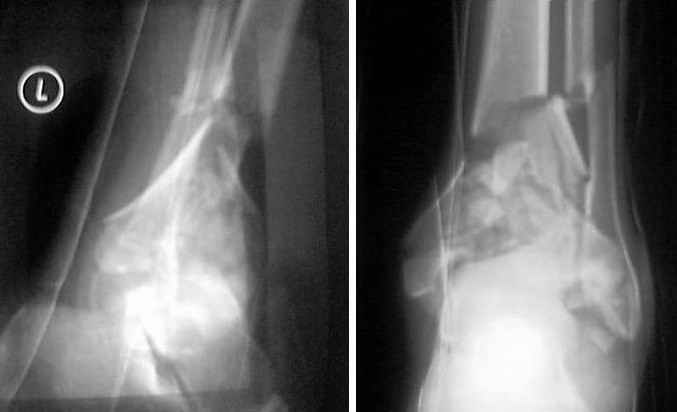

Pilon fracture:

This is a pilon fracture. I suggest fixation of the fibula with a one-third tubular plate and a joint spanning external fixator on the medial side as initial treatment. If the tibial articular surface cannot be reconstituted, the patient will require an arthrodesis.

I would suggest to fix the fibular fracture at the very beginning and under fluoroscopical control and axial traction try to restore articular surface stabilizing percutanously by K wires and cannulated screws, type of external fixation to be used is up to your preference.